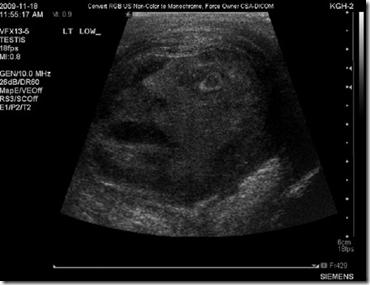

Publicado pela Sociedade Internacional de Urologia, a imagem de um rosto humano apareceu no ultrassom de um homem de 45 anos de idade que tem câncer nos testículos.

A imagem é tão nítida que é possível ver o que parece o desenho de um rosto com boca, nariz, olhos e até o contorno do da cabeça e as linhas da testa.

"Os médicos residentes e a equipe do hospital ficaram impressionados ao ver as feições de um homem na imagem", menciona a publicação.